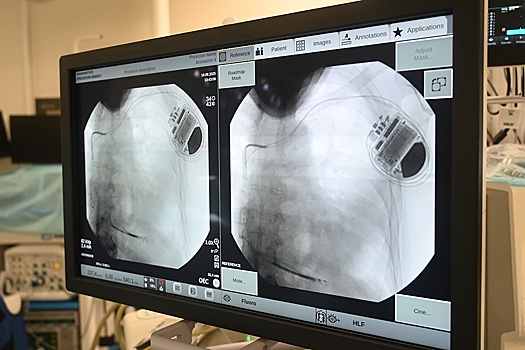

Подкожный кардиовертер-дефибриллятор устанавливается под широчайшую мышцу спины в подмышечной области, а электрод проводится подкожно на переднюю грудную стенку и устанавливается в проекции сердца. Прибор контролирует активность сердца и, когда оно останавливается, начинает биться неправильно, слишком медленно или слишком быстро, благодаря специальным алгоритмам аппарат посылает электрические импульсы, позволяющие восстановить нормальный сердечный ритм.

Впервые подкожную систему кардиовертера-дефибриллятора установили пациенту медики больницы им. В.В. Вересаева год назад. Сегодня такие вмешательства проводят в операционных ГКБ им. С.С. Юдина, ГКБ им. В.В.Вересаева и ГКБ им. И.В. Давыдовского.